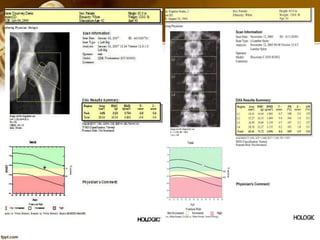

AP Lumbar Spine Exam

 Correct Spine ROI

• The spine is in the center of

the image including all L1-L4

vertebrae.

• (1) All of L4 (1) is shown.

• (2) The top of L5 (2) is shown.

• (3) Approximately lower half

of T12 (with ribs) is shown.

 Spine ROI

• Use High definition for patients

with heavy weight.

• Cover from L1-L4

• The Lines have to be parallel to

intervertebral space.

• Avoid Metals

• Delete osteophyte

 Positioning the Patient and C-arm

• The goal for positioning the patient

on the table is to ensure that the

hip is as straight as possible for the

scan.

• Positioning the patient for a hip

scan involves using the Foot

Positioner. This positioner helps to

align the patient’s hip and holds

the foot firmly in place.

• Laser adjust 3 inches below the

greater trochanter and 1 inch

medial to the shaft of the femur.

AP Hip Exam